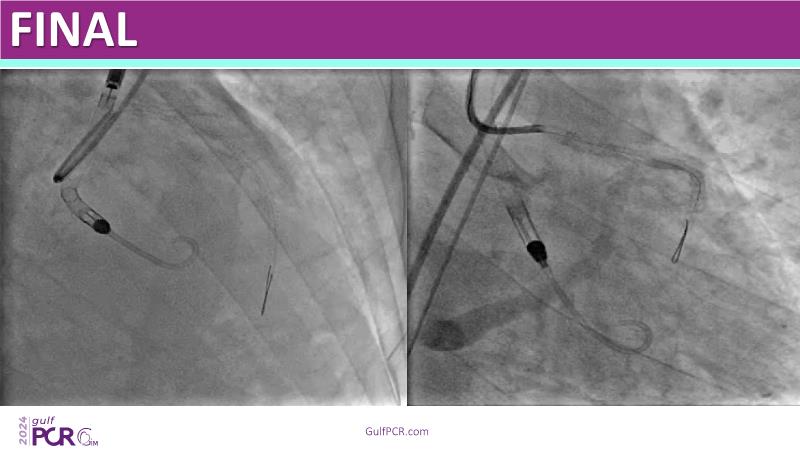

This session highlights the essential role of mechanical circulatory support (MCS) in managing high-risk PCI and AMI-related cardiogenic shock. Explore case-based discussions on device selection, hemodynamic impact, and evidence-based strategies to optimize outcomes in complex scenarios.